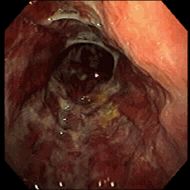

As alterações da gastropatia hipertensiva portal são mais evidentes na mucosa do corpo e fundo do estômago. Os aspectos endoscópicos incluem um padrão de eritema fino, difuso e pontilhado, rash escarlatiniforme ou o padrão conhecido como “pele de cobra” ou “mosaico”, onde se observa áreas avermelhadas, pequenas e poligonais delimitadas por bordas deprimidas e amarelo claras5-8. A gastropatia severa é caracterizada pela presença de pontos vermelho escuros ( “cherry red spots” ) e áreas de hemorragia mucosa difusa ( “gastrite hemorrágica” )5,8. Em estudos endoscópicos com grande amostragem de cirróticos assintomáticos, mais que 50 % apresentam sinais de gastropatia hipertensiva portal, sendo o achado mais comum o padrão mosaico ou em pele de cobra no estômago proximal8,9.

Em 1994, o NIEC (New Italian Endoscopic Club) propôs nova classificação para padronizar as descrições da gastropatia hipertensiva portal10. A classificação se baseia em 4 sinais endoscópicos elementares (tabela 2).

| Classificação da gastropatia hipertensiva portal (Milão –1994) |

| 1. Padrão mosaico ( mosaic-like pattern – MLP ), graduado como leve, moderado ou severo |

| 2. Marcas vermelhas ( red marks – RM ), que incluem lesões puntiformes vermelhas ( red point lesions – RPL ) e pontos vermelho cereja ( cherry red spots – CRS ) |

| 3. Pontos marrom escuros ( black Brown spots – BBS ) |

TRATAMENTO